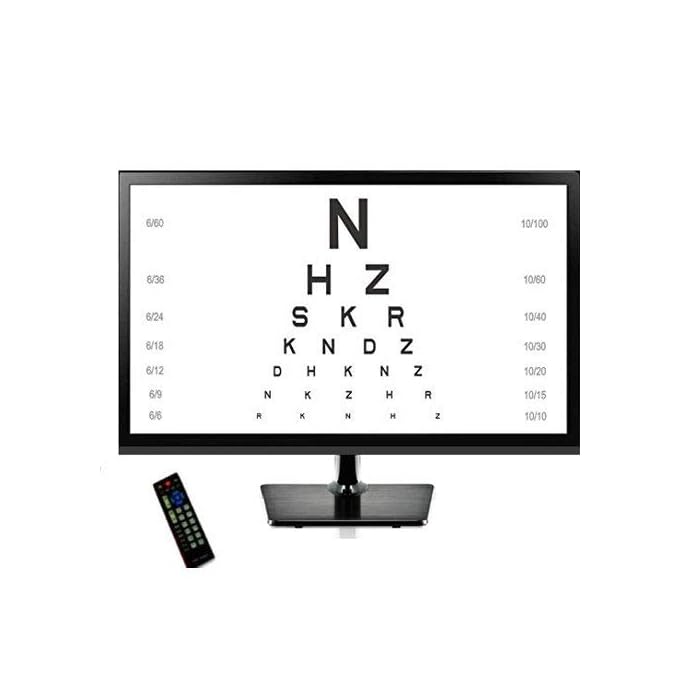

DIGITAL VISION CHART

DIGITAL VISION CHART